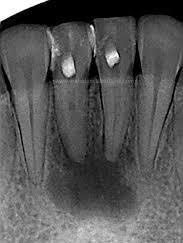

El objetivo del presente artículo, es describir los efectos secundarios de la radioterapia en cavidad bucal, principalmente en lo referente a la osteorradionecrosis, haciendo énfasis en la prevención, en la cual juega un papel muy importante la terapia endodóntica.

La Imagen 1 muestra la acción de la radiación ionizante sobre un átomo.

Pulpitis y necrosis pulpar

Una de las consecuencias más importantes que provoca la radioterapia en los dientes es la patología pulpar. Se destruyen los odontoblastos y se forma una fibrosis pulpar. Aunado a esto, la caries radiogénica agrega infección bacteriana en la pulpa, inflamación, microabscesos y finalmente necrosis.